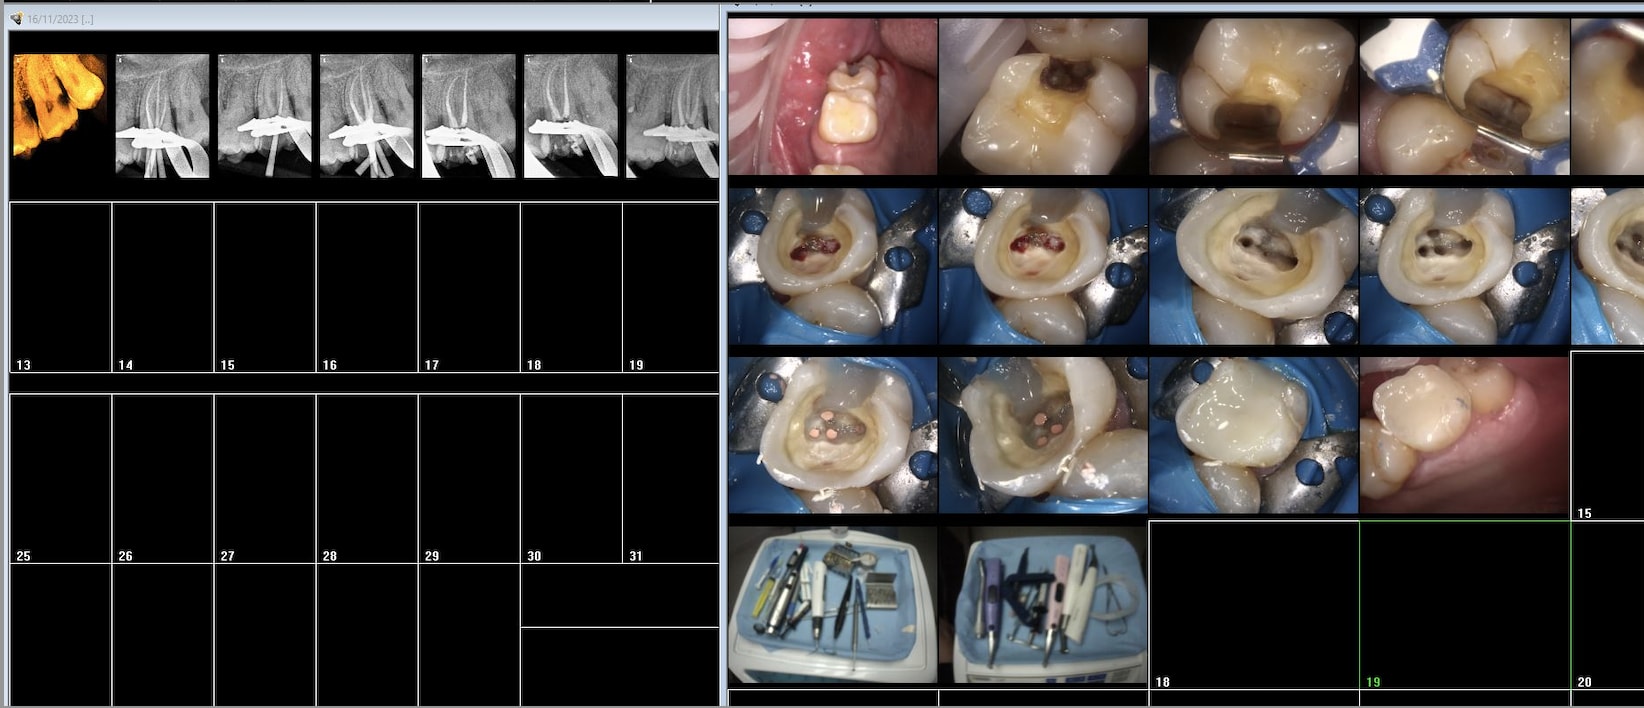

Mais binbin il a pas pris des photos de ses assainissements parodontaux fictifs. Tu factures tu en apportes la preuve . point . binbin.

Le motif était les douleurs secteur 1. La dent causale est pour moi la 17 avec importante lipoe et douleurs à la percussion.

Les 13 et 15 étaient, d’après le devis, nécrosées. Il y a eu des rcpe devisées pour les deux dents puis des reconstructions de moignons sans ancrage.

Ras en 13 et 15 si ce n’est la reprise de carie. Je ne suis pas certain que les couronnes aient été faites par cet endo mais je revois le patient pour sa 12 et lui demanderai.

Et si t'avais l'habitude d'en faire tu t'apercevrais que c'est pas si facile que ça à matricer en sous gingival.

C'est con parceque quand tu fais pas de RCPE tu peux quand même les facturer les photos avec tact et mesure. -)

tu dis que t'en fais rarement alors que dans 90 % du temps tu dois en faire une. binbin.